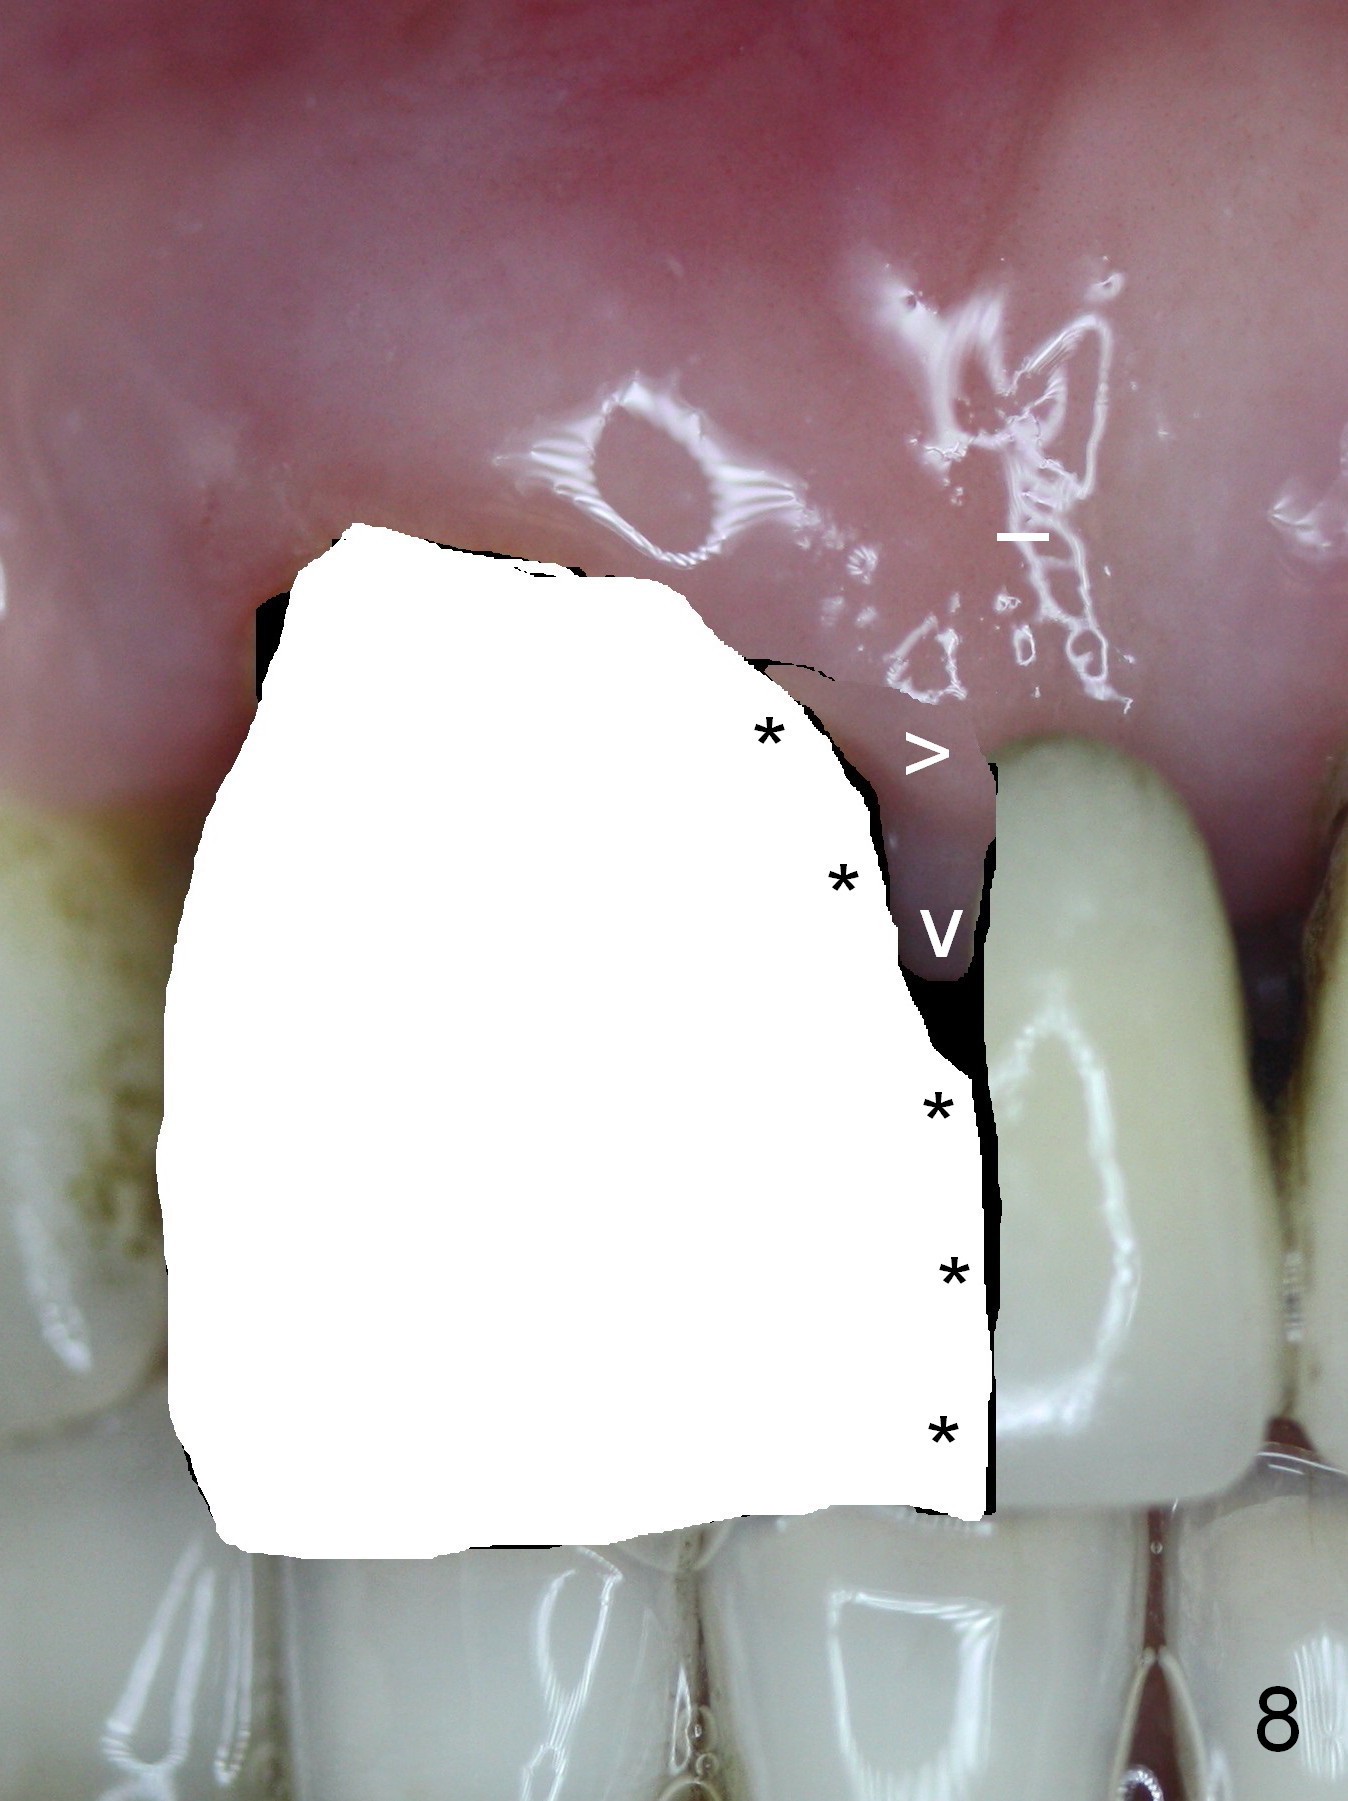

The 74-year-old patient is excited about having 3 implants placed without discomfort (1,2). He wants to take care of a loose FPD spanning from #8 to 9 (Fig.1). It appears that #8 is non-salvageable (Fig.2 * with deep pockets). There is severe bone loss around the affected tooth (Fig.3; Osteotape is expected for buccal and lingual defects). In addition, the Incisive Canal is abnormally large (arrowheads). The coronal end of a 4.5x20 mm implant and a 3.5x5 mm abutment will be slightly deviated mesially (Fig.4), since the 3-unit FPD will be converted to 2 single unit crowns. Surgical guide is ready. The 1st step is to section between #8 and the pontic (Fig.5; green outline: implant; red: abutment). If primary stability is low, the immediate provisional (Fig.8 white area) will be bonded the tooth #7 and the pontic as a supplementary measure (blue areas). Once the implant is osteointegrated, the distal portion of the pontic (Fig.7 *) will be removed. Acrylic is added to the mesial portion of the provisional (Fig.8 *) so that the papilla (P in Fig.7) will be pushed mesially and incisally (Fig.8 arrowheads). The step will be repeated a few weeks later (Fig.9). It could be done bilaterally at the same time by removing #9 crown and converting to the provisional. Finally the pontic will be removed. Two relatively wide crowns will be fabricated if the patient is satisfied with the provisional.